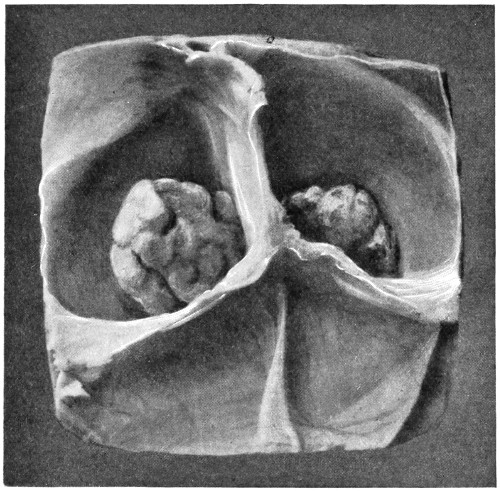

| 62. A glioma of the brain | 211 |

| 63. A sarcoma of the brain | 211 |

| 64. An endothelioma of the dura mater | 212 |

| 65. A fibroma of the dura mater | 212 |

| 66. An acoustic tumour | 213 |

| 67. Symmetrical tuberculomata | 214 |

| 22. An occipital cephalocele | 37 |